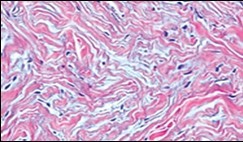

Figure 4.Soft tissue perineurioma composed of whorls and perivascular aggregates of neural cells with bipolar cytoplasmic processes, wavy, slender nuclei and commingled collagen fibres 13.

Soft tissue perineurioma composed of whorls and perivascular aggregates of neural cells with bipolar cytoplasmic processes, wavy, slender nuclei and commingled collagen fibres 13.